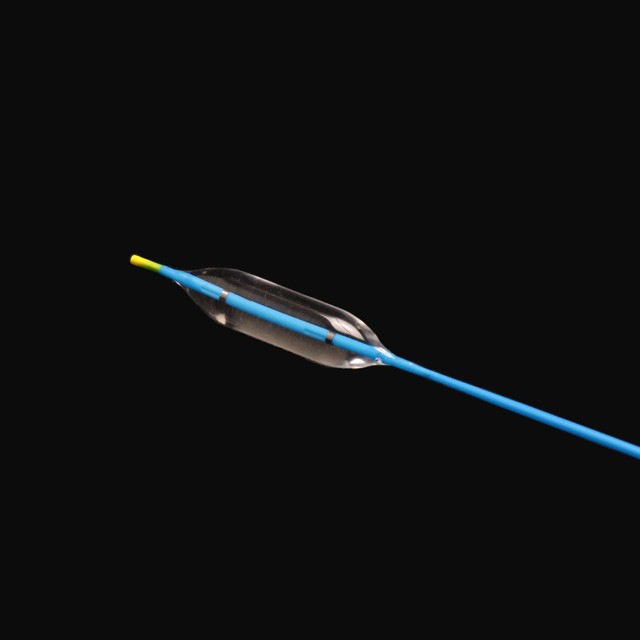

●Elastiskt mjúkt tips design,sum kann snúgva seg um markstøðuna við minni skaða{0}}

●Brúka innflutt tilfar við hátrýstmótstøðu og tryggari dilatatión.

●Optimal sniðgeving av rørinum ger tað slætt og av góðari elastisiteti,sterk snúningsmótstøða og lættari gjøgnumgongdir{0}}